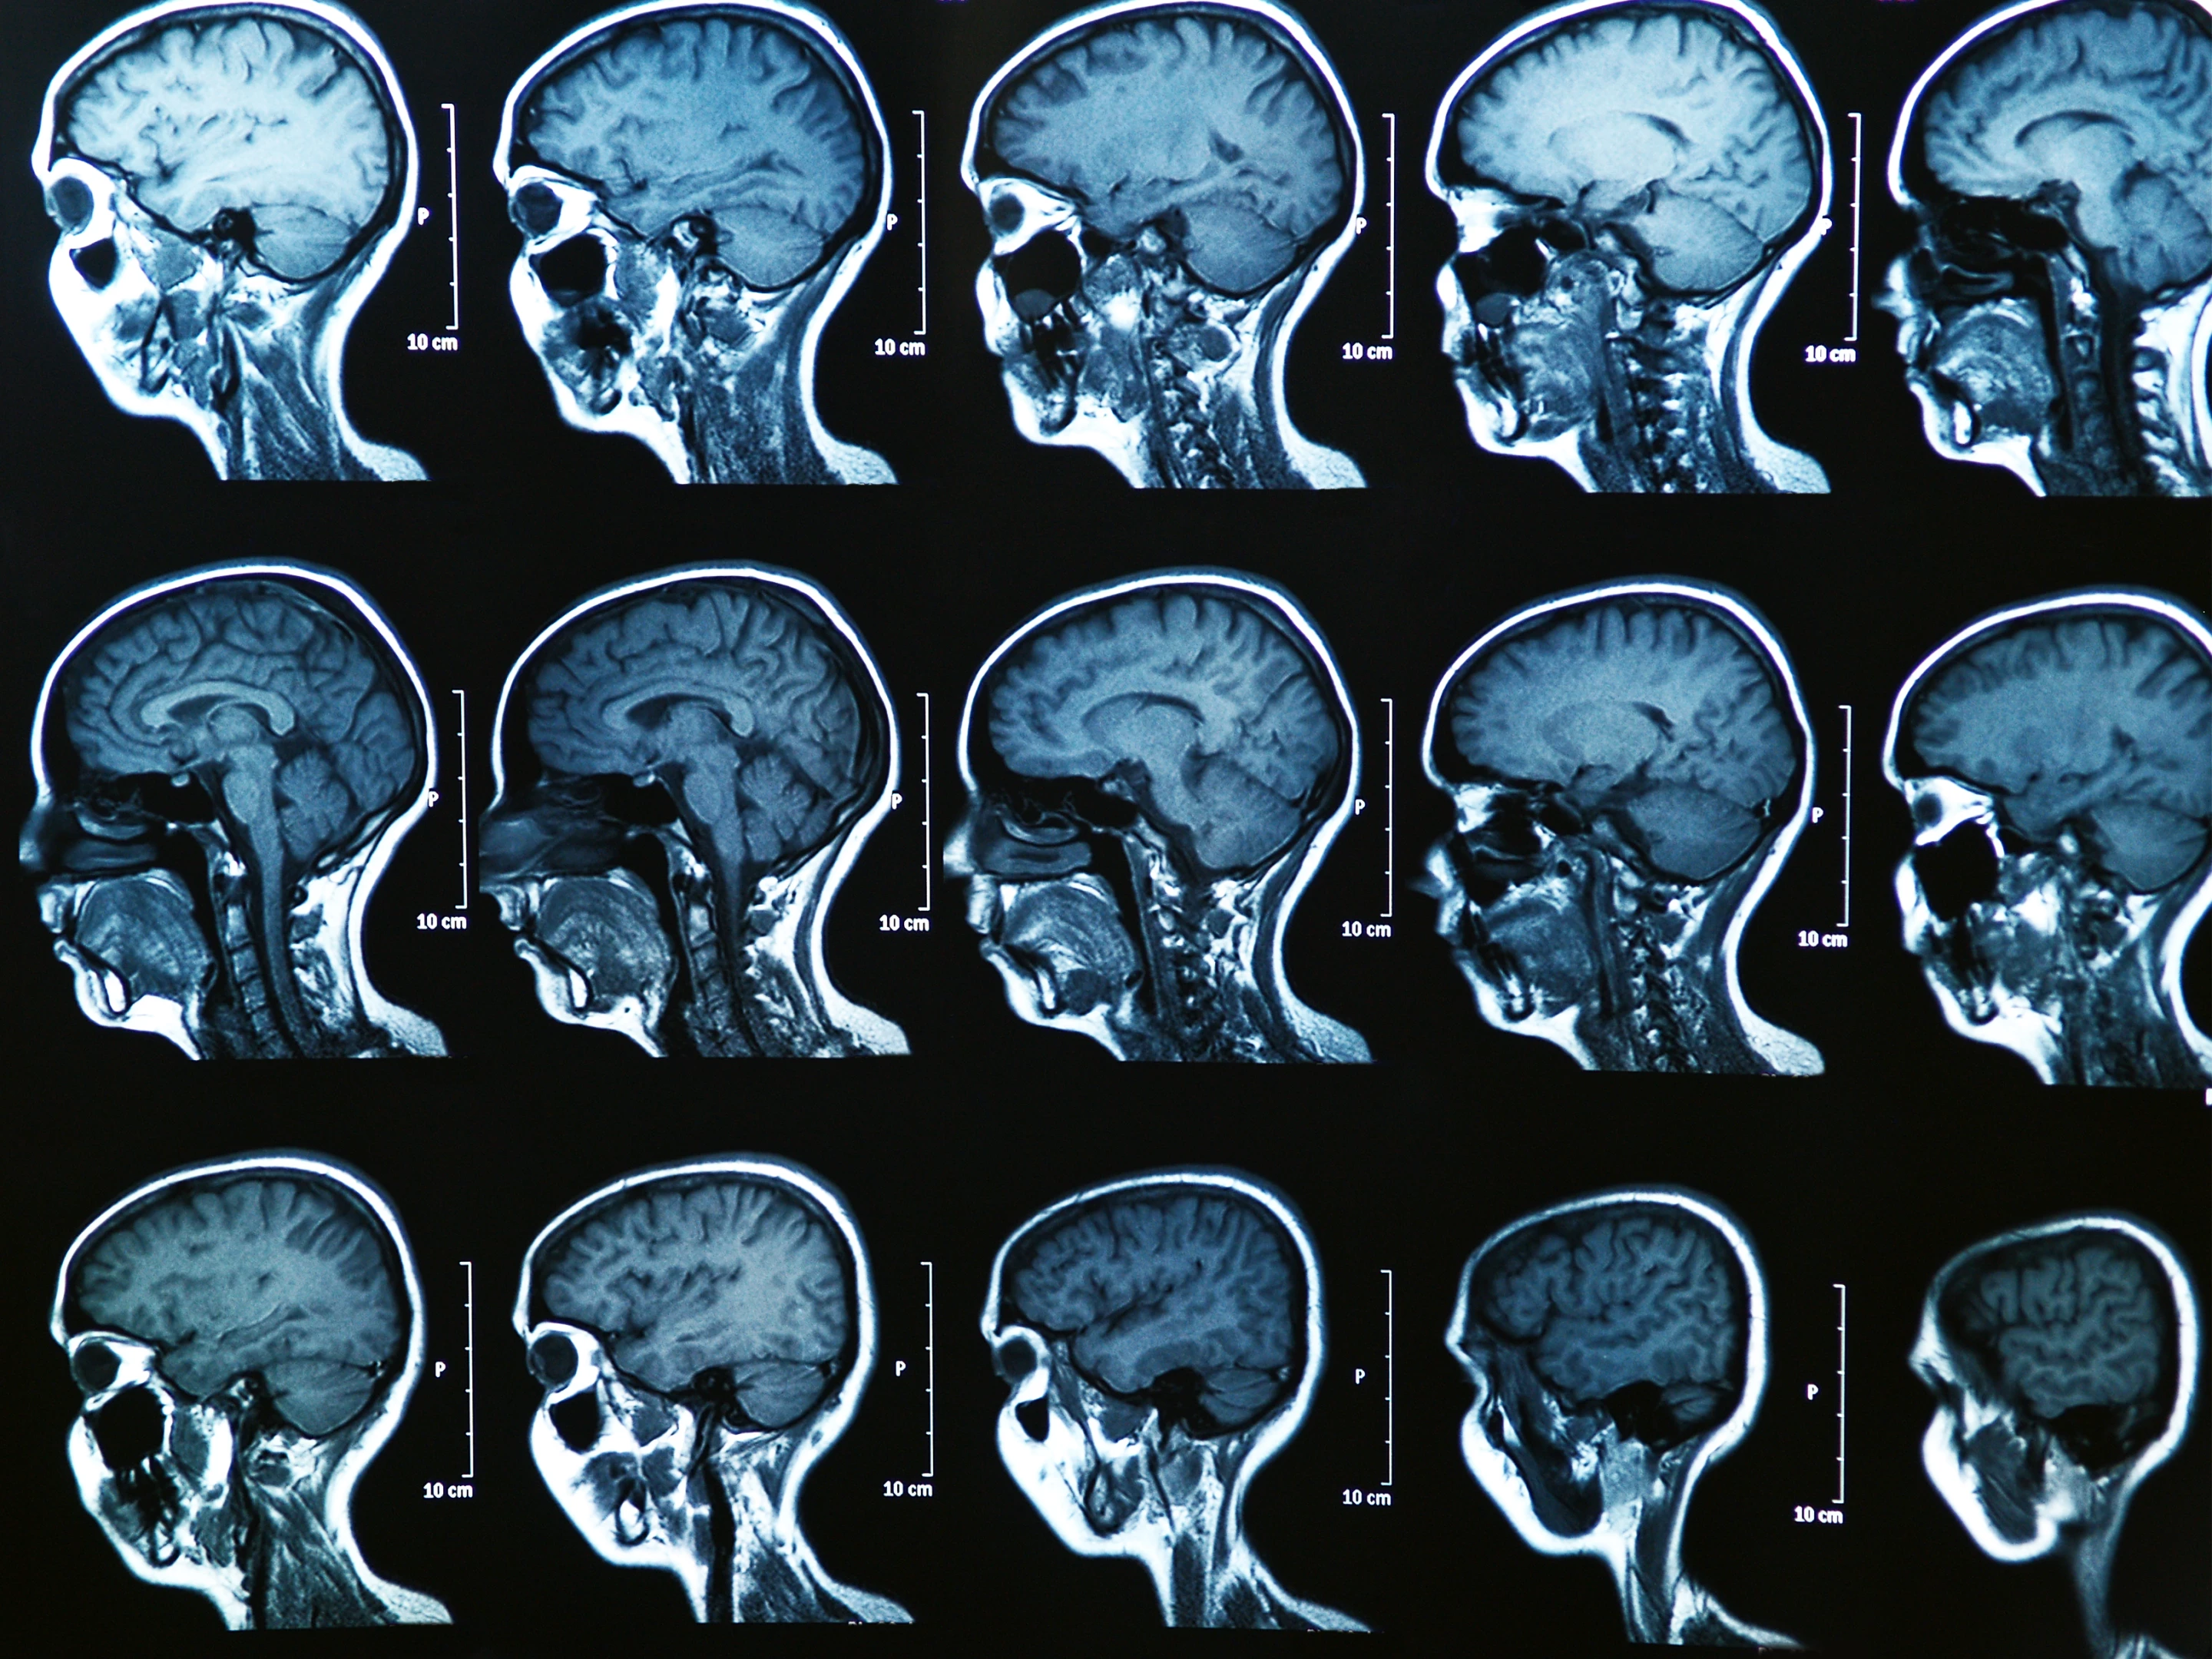

Fifty years on from American chemist Pal Laterbur detailing the first magnetic resonance imaging (MRI), scientists have marked this historic medical anniversary with the sharpest-ever scans of a mouse brain.

This MRI was able to capture images in such detail that each voxel – the 3D version of a pixel – measured just 5 microns, or five-thousandth of a millimeter. What this means is that while current MRI technology is advanced enough to spot a brain tumor, for example, this sort of clear picture can take things a step further and display organization and far more detailed connectivity.

The MRI was able to capture incredible images of circuitry data throughout the mouse brain, as shown in the video below.